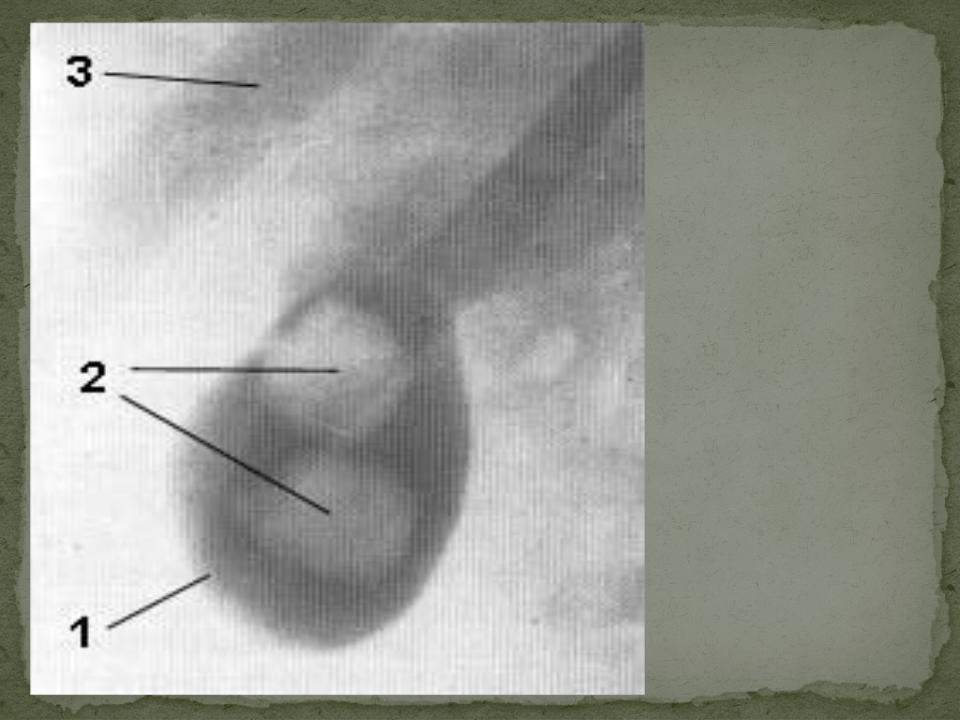

Анатомия и особенности Гартманова кармана желчного пузыря